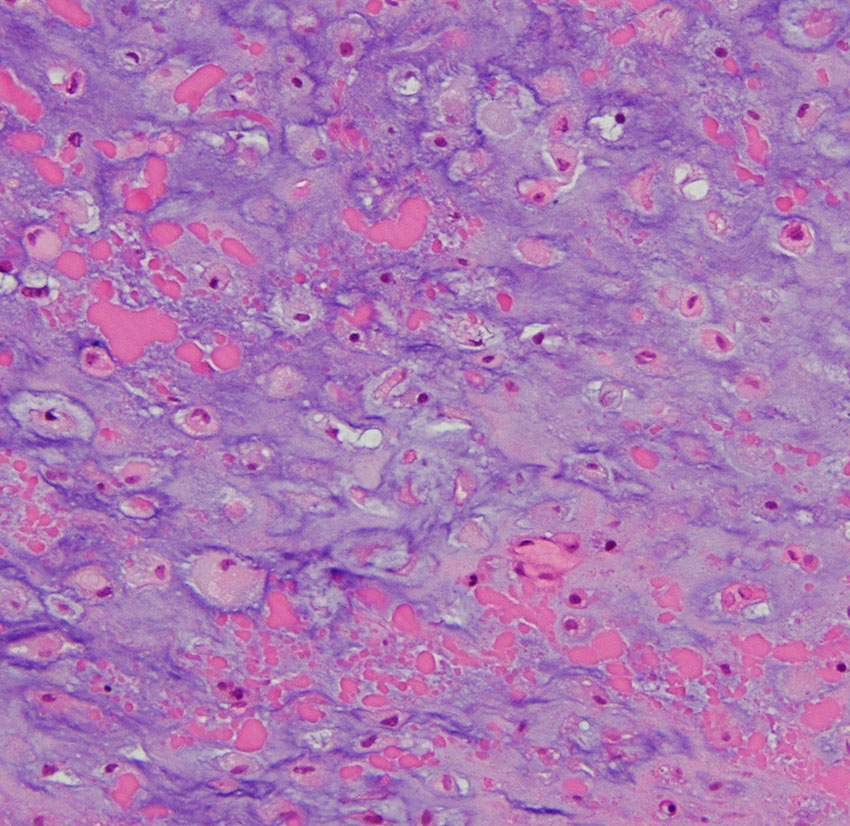

低悪性度軟骨肉腫の病理像 grade 2 chondrosarcoma

背景は好塩基性の軟骨基質(粘液状 myxoid,軟骨様 chondroid)です。好酸性胞体をもつ異型紡錘形ないし上皮様細胞が多結節状に増殖しています。細胞密度はやや高い部分もあり,核は濃縮され大小不同や2核の細胞も見られます。MIB-1 index 3%